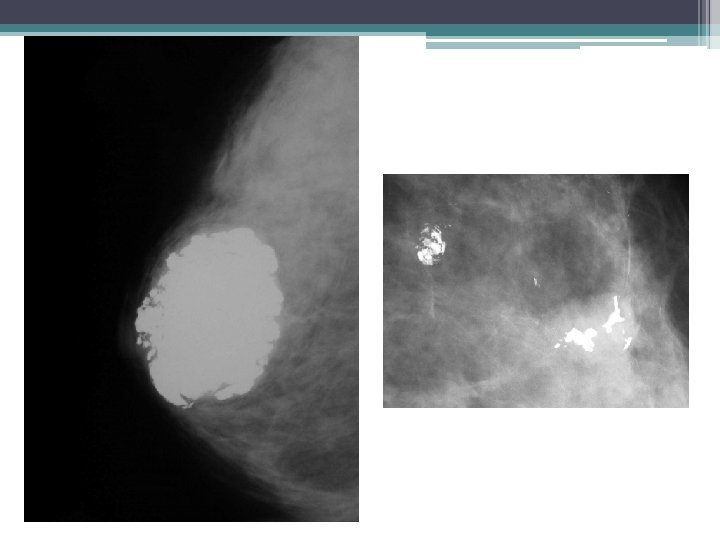

TUMEUR PHYLLODE • MAMMOGRAPHIE: ▫ Opacité dense, arrondie, hétérogène, ▫ polylobée, bien limitée, ▫ unique et de grande taille • ECHO: ▫ Formation solide bien limitée, de contours lobulés ▫ Echostructure +/- hétérogène, pfs renforcement postérieur ▫ Remaniements kystiques ou micro kystiques: évocateur de la lésion

TUMEUR PHYLLODE • Les arguments en faveur de la malignité sont : ▫ La taille supérieure à 3 cm, ▫ La présence de microcalcifications, ▫ La présence de remaniements microkystiques. • La biopsie-exérèse large++

ADENOFIBROME • MAMMOGRAPHIE: ▫ ▫ Opacité dense, ronde ou ovalaire, bien limitée Contours nets, polylobés halo radio transparent Calcifications �typiques: grossières, confluentes, (pop corn) �atypiques: punctiformes ou linéaire